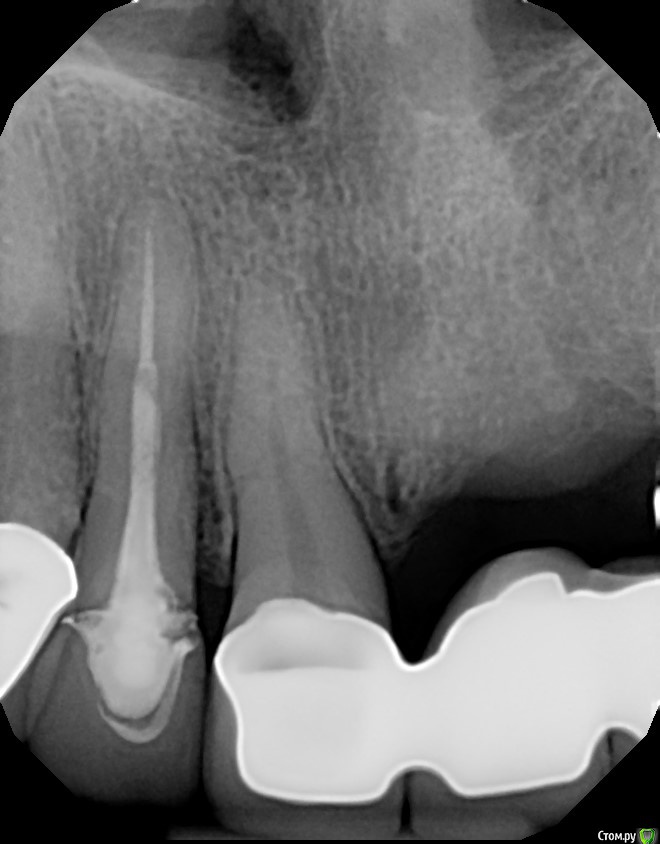

Dirina12 Опубликовано 14 июля, 2017 Автор Поделиться Опубликовано 14 июля, 2017 Спасибо за отзыв. А какой зуб с сомнительным прогнозом ?Конечно , в идеале я понимаю,что лучше все снять, пролечить и поставить новые коронки и мосты. Но здесь в Америке, ето целое состояние .А что можете сказать об етом зубе ( номер 7). Мне предстоит во вторник резекция и пломбирование сверху корня. Удастся ли спасти зуб? Стоимость $2К. Ссылка на комментарий